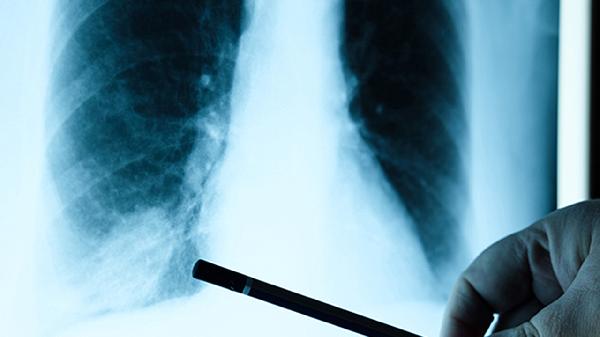

二、肺癌早期的咳嗽特點

咳嗽是身體發出的重要信號,既不必過度緊張,也不能掉以輕心。當咳嗽出現文中提到的特殊表現時,建議及時進行胸部CT檢查。記住,早期發現永遠是應對疾病最有力的武器。現在放下手機,做個深呼吸,感受一下你的肺部是否在舒適地工作?